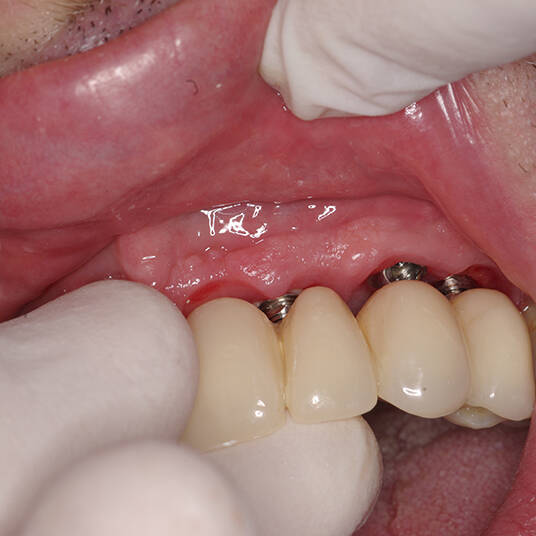

Na Clínica Pontes Odontologia, somos referência em implantes dentários em Fortaleza, oferecendo tratamentos de alta qualidade e tecnologia de ponta. Os implantes dentários são estruturas de titânio posicionadas cirurgicamente no osso maxilar ou mandibular para substituir as raízes dos dentes ausentes. Essa técnica permite a fixação de próteses personalizadas, restaurando a função mastigatória, a estética e a autoestima dos nossos pacientes.

Utilizamos a tecnologia CAD CAM, um sistema avançado que possibilita a confecção precisa das próteses dentárias diretamente sobre os implantes. Esse método inovador garante um ajuste perfeito, um resultado estético superior e proporciona muito mais conforto e durabilidade. Com o CAD CAM, nossos pacientes contam com um processo mais rápido e previsível para alcançar o sorriso desejado.